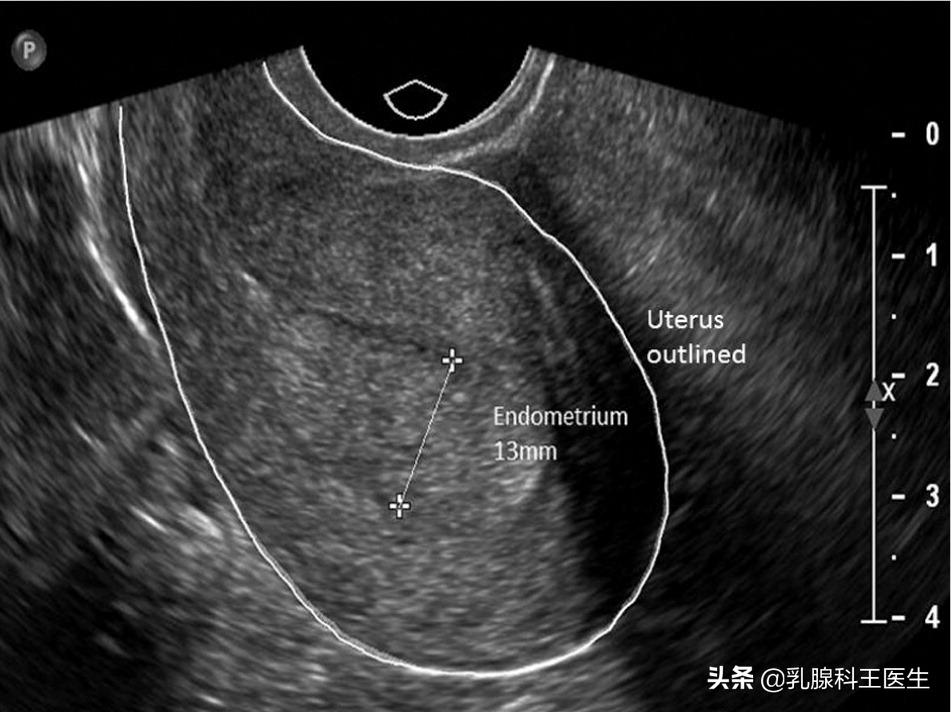

研究显示,使用他莫西芬的患者会出现子宫内膜增厚,有报道称,服用他莫西芬的患者,子宫内膜厚度每年增加0.75mm,停止服用他莫西芬后,子宫内膜每年变薄1.27mm。对于没有任何症状的子宫内膜增厚一般不需要特殊处理。有专家共识认为19mm以下一般不需要特殊处理。之前我的一位患者内分泌之治疗后3个月子宫内膜厚11mm,不放心,在妇科做了诊刮,病理提示子宫内膜单纯性增厚,也就是说没问题。

大部分情况下不伴有明显症状如不规则阴道出血或绝经后阴道出血,无异常血性分泌物的子宫内膜增厚一般问题都不大。再结合超声诊断,如果无阳性发现,阳性发现包括血管形成增加,子宫内膜不均匀,颗粒状液体,子宫内膜过厚>11mm,这些超声下的阳性表现没有的话可以不用管,3月后复诊再看结果。

虽然致癌风险较低,但在服用他莫西芬期间一年要做1-2次例行的妇科超声检查,最好在月经结束后3-5天去。因为在月经前期子宫内膜也会增厚,一般会达到12-13mm,所以检查时间也很关键,不能用这种数值和月经结束后的数值比较。其实在临床上乳腺癌术后内分泌治疗发现子宫内膜癌的很少,即便有也是早期,效果很好的。但是内分泌治疗的长期获益是很可观的,因此不能因此担心子宫内膜增厚或者概率很小的子宫内膜癌风险就拒绝内分泌治疗,或者吃五天停两天,这都是不可取的。